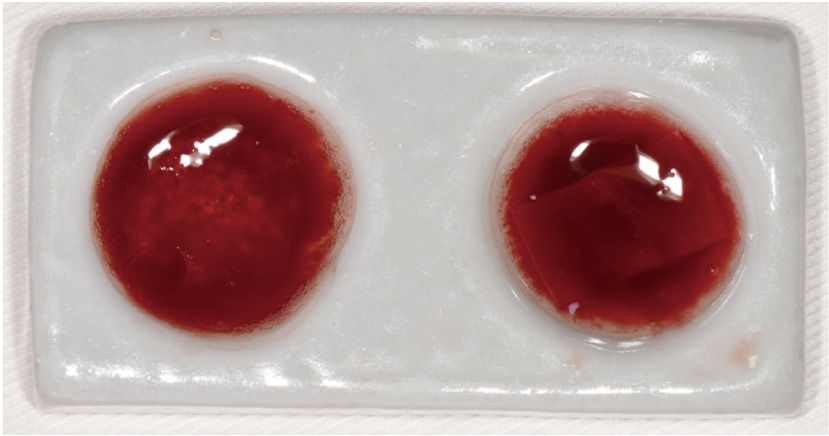

Effect of concentrated growth factors in guided tissue regeneration for the treatment of mandibular molar furcation lesions

| [14] | Fei LI,Jing QIAO,Jin-yu DUAN,Yong ZHANG,Xiu-jing WANG. Effect of concentrated growth factors combined with guided tissue regeneration in treatment of classⅡ furcation involvements of mandibular molars [J]. Journal of Peking University (Health Sciences), 2020, 52(2): 346-352. |

| [5] | Xinying WANG, Xueyuan CHENG, Yong ZHANG, Fei LI, Jinyu DUAN, Jing QIAO. Therapeutic effect of concentrated growth factors combined with self-curing calcium phosphate cement on periodontal intrabony defects: Clinical and radiographic evaluation [J]. Journal of Peking University (Health Sciences), 2025, 57(1): 42-50. |